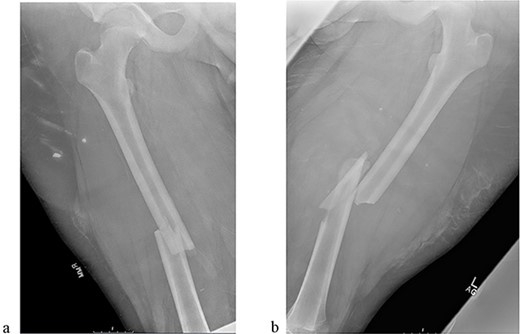

The patient tolerated the procedure well and recovered uneventfully. He was noted to have circumferential osseous healing at 1 year and underwent bilateral femur IMN removal 1.5 years postoperative without complication (Figs 4a–d and 5a–d).

(a) Right femur AP radiograph after implant removal. (b) Right femur lateral radiograph after implant removal. (c) Left femur AP radiograph after implant removal. (d) Left femur lateral radiograph after implant removal.